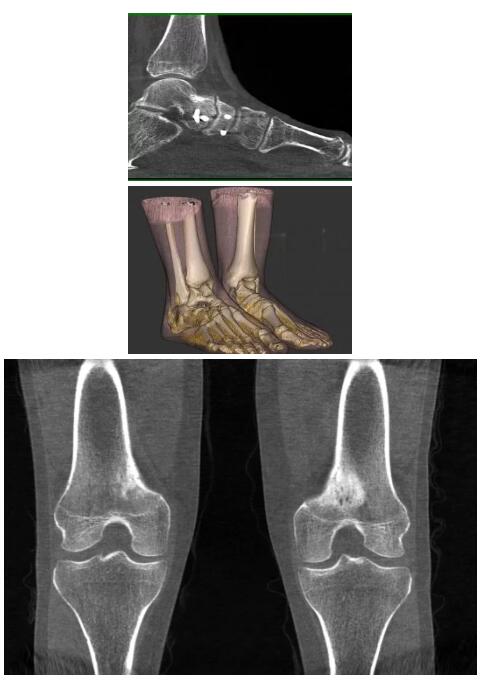

比如上面這款專用于足部和踝部掃查的CT成像系統(tǒng),患者在進行CT掃查時只需要站在上面即可,雙腳站或者單腳站都可以,當然,如果患者不是那么方便站著做完CT掃查,也可坐在上面。

這款CT掃查系統(tǒng)自帶屏蔽裝置,它的體積非常小,僅需要極小的空間即可,并不像常規(guī)CT那樣需要一間單獨的檢查室。此外,這種CT掃查的速度非???,僅需30秒左右可以完成檢查,輻射劑量相對常規(guī)的CT要少許多,尤其適合醫(yī)院的骨科使用。

而患者站著做足部或者踝部做CT檢查還有個好處是,可以檢查患者在負重的情況下,骨關(guān)節(jié)的真實情況,而躺著做CT掃查時未必能看出來。負重CT掃查特別是對于受傷的運動員或者舞蹈員來說意義更大,能夠更準確地評估傷情,幫助他們盡早復(fù)原。

另外一款被稱為世界上最小的CT,它的重量僅300磅,不僅能夠掃查足部,還可以檢查膝蓋和上肢等。

與上面介紹的CT一樣,它同樣具有輻射低、占地空間?。?3*36)的特點,隨開隨用(支持直接接入墻上的插座)。

這款CT使用非常方便,通過上下移動保持與患者的手臂或者雙腿齊平,掃描快速,僅需要30秒左右就可以完成掃查。

以上介紹的CT均來自國外同一家公司,這些CT均配置了可視化軟件,可以進行切片、3D重建以及大型CT附帶的所有典型的操作功能。

以下是這些“特立獨行”的CT所拍出來的圖像: